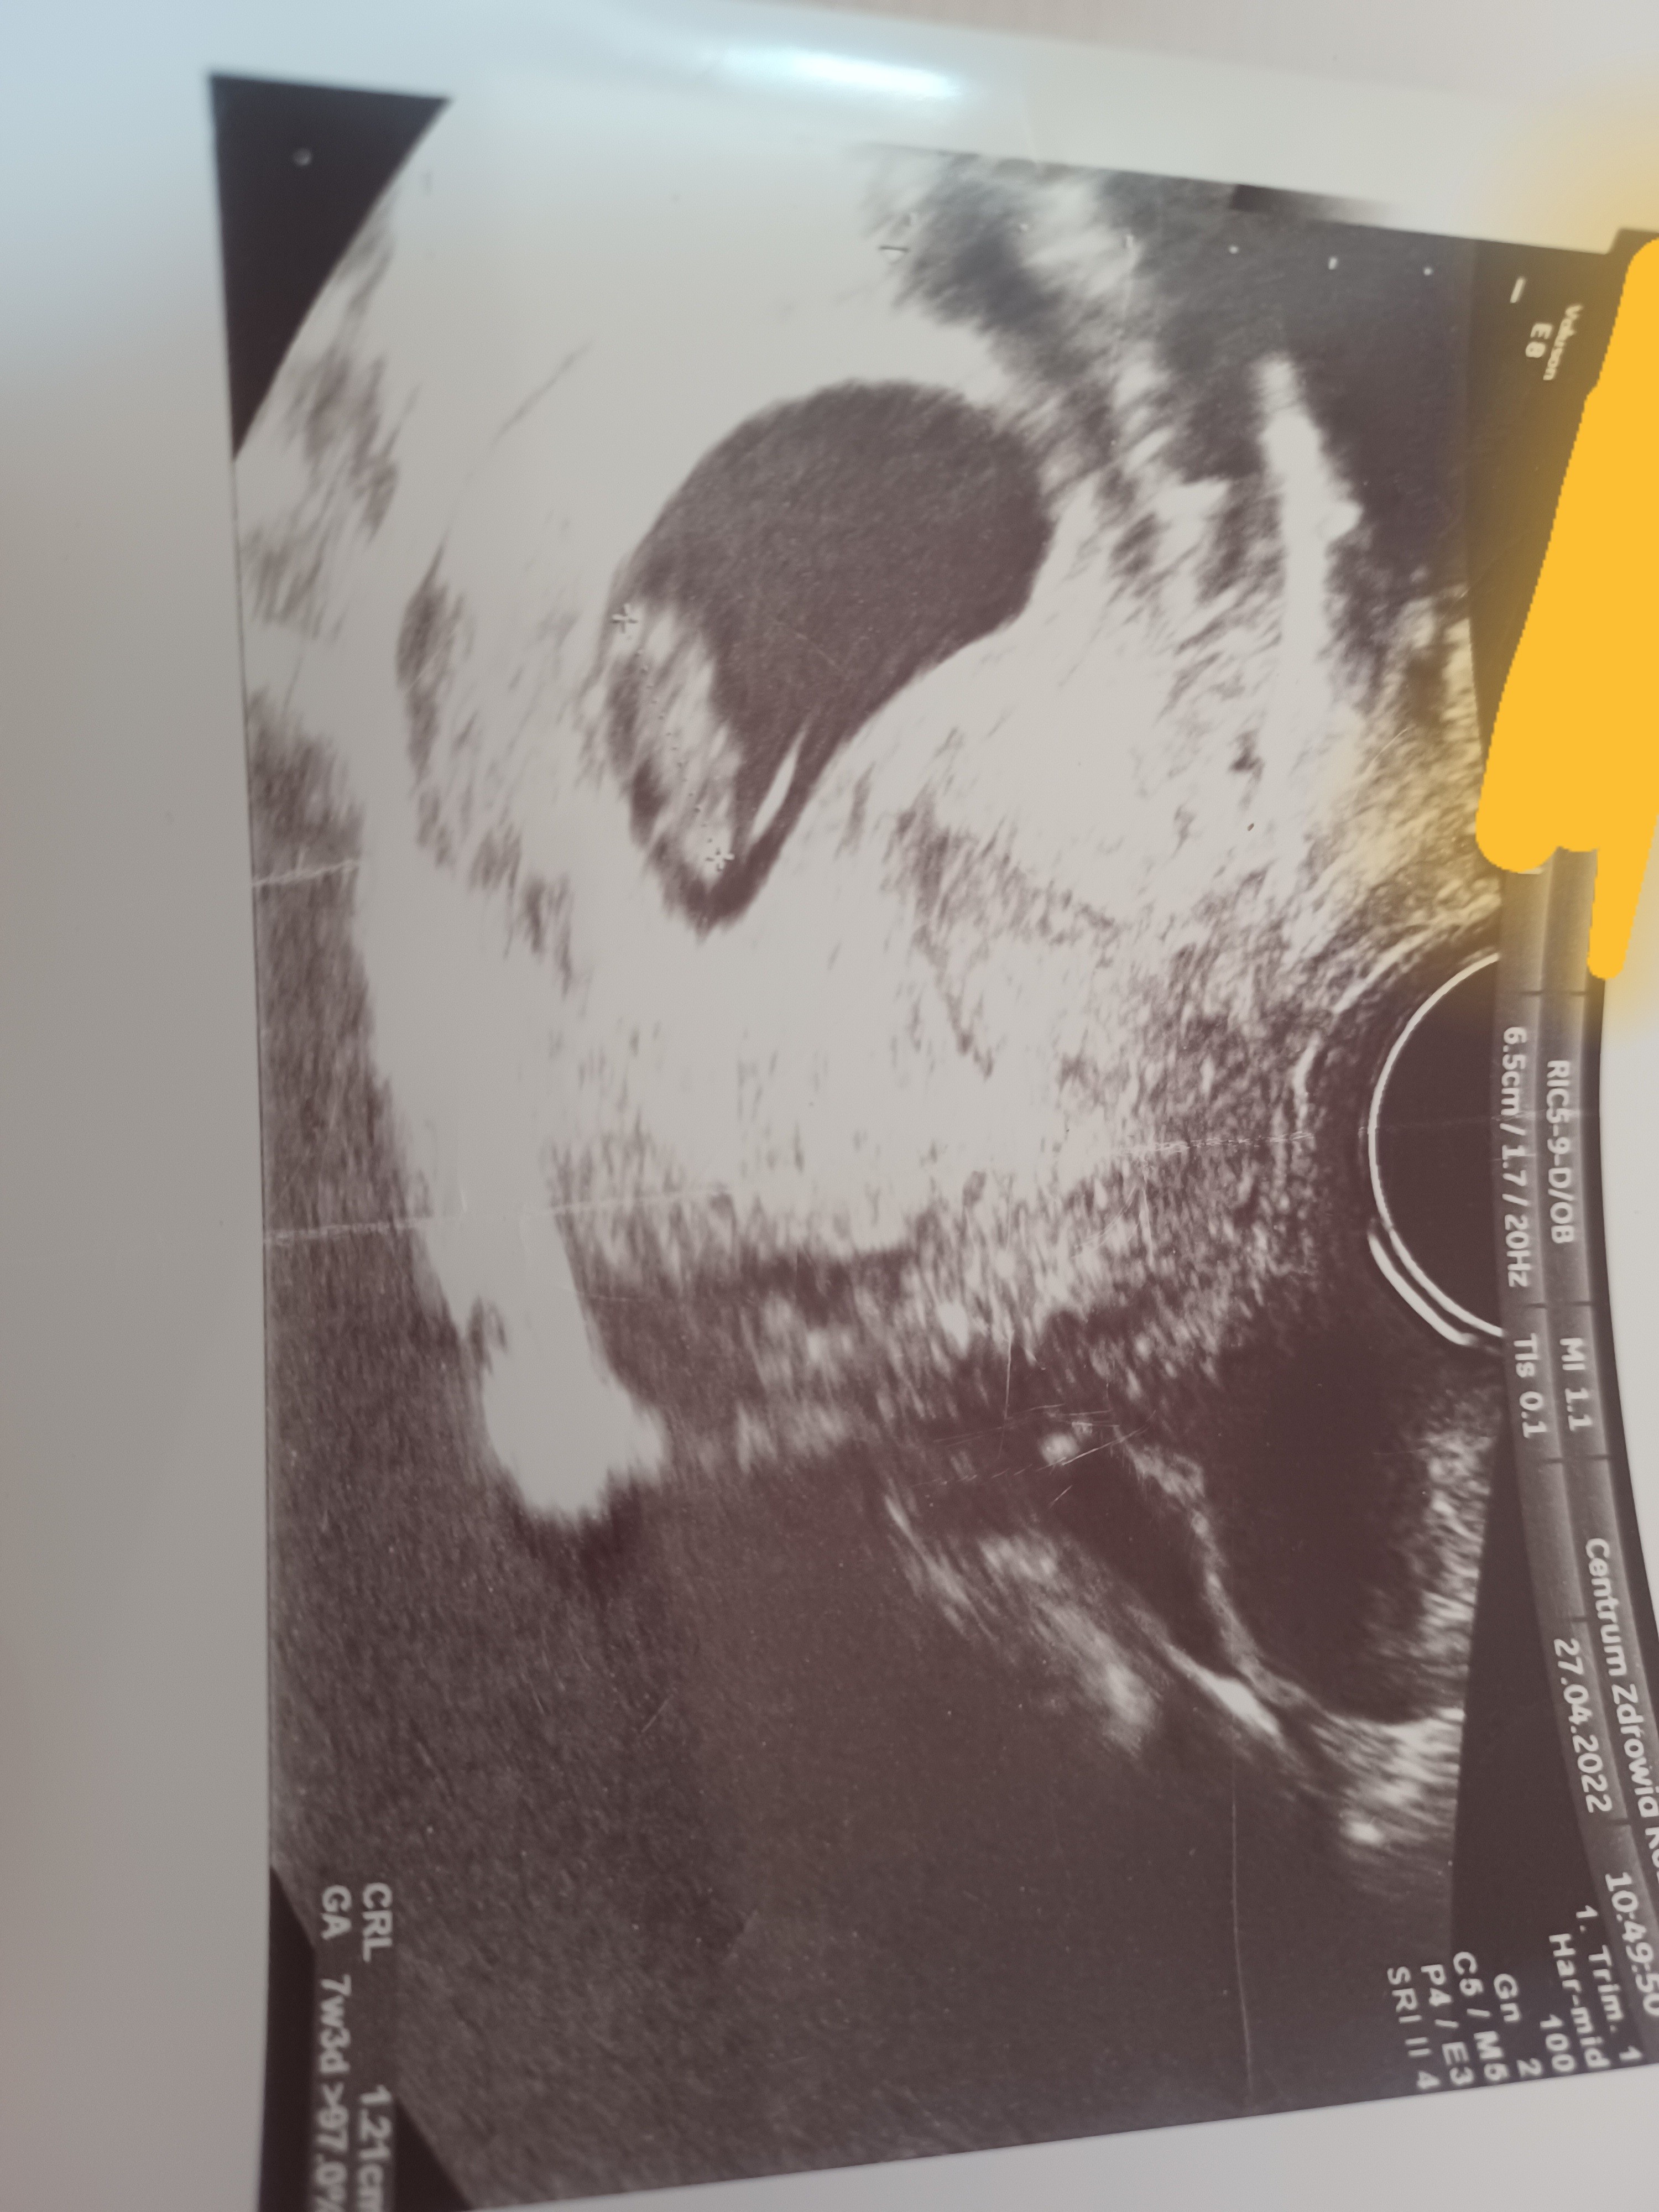

Hej dziewczyny czy jesteście w stanie przypuszczać po tych usg jaka to płeć dziecka? Mam przeczucie ze to chłopiec a jak waszym zdaniem? To wszystkie usg jakie posiadam.

• 20220713_180001.jpg

20220713_180001.jpg

1,6 MB · Wyświetleń: 292